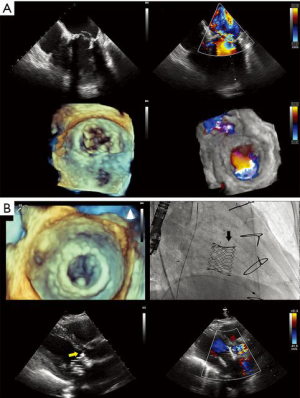

- Edge to edge repair. MitraClip® technology replicates the Alfieri edge-to-edge stitch repair of MR and is exclusively driven by echocardiography (Figure 9, Video 3). It has been used in >50,000 patients, with FDA approval limited to DMR as a class IIb indication in patients with prohibitive surgical risk. It achieves MR reduction and may preclude surgical repair in failed cases (5). The echocardiographic patient selection criteria and the intraprocedural guidance principles have been extensively described (5,27,28). Experienced operators commonly obtain patient, procedural and technical success, with acceptable device success, as defined by MVARC (9). The long-term hemodynamic impact of MitraClip® implantation has been less enthusiastically studied. Echocardiography-based mitral valve sizing and regurgitation quantification relies on several assumptions: single, static, rounded regurgitant orifice and single, central, non-eccentric, holosystolic jet, without associated MS. Post-clip deployment, these assumptions are violated, as a double orifice is created, frequently accompanied by two regurgitant jets. Area measurement of the double orifice is limited to the planimetry of cross-sectional views. A definition of MS post MitraClip® patients does not exist; a pressure halftime of >91 m/sec was found to correlate with high post-procedural gradients. Post-procedural mitral gradients are difficult to predict. Typically, they are mildly elevated compared to baseline and tend to not increase proportional to the number of clips implanted, even at higher heart rates, but raise significantly with exercise echocardiography. The residual regurgitation evaluation is limited to semi-quantitative color Doppler data, as PISA method is not validated for double orifices and jets. The impact of a persistent interatrial defect and shunt is not well understood and closure is advocated in patients with pulmonary hypertension and failing right ventricles. Notably, recent data shows absence of post implant LV remodeling in patients with LVEF <40%, in contrast with earlier reports (29). Imaging MitraClip® patients remains largely operator-dependent requires development of specific criteria to clearly define device success and complications.

- Mitral annuloplasty. Largest experience stems from two TEE guided devices: Carillon® Mitral Contour System® and Cardioband® Mitral Valve Reconstruction System (30,31). Carillon® is deployed into the coronary sinus via transjugular approach, then the device is anchored near the antero-lateral commissure, followed by plication of the peri-annular tissue, without general anesthesia, in FMR patients. A favorable anatomy of the coronary sinus in relation with the mitral annulus and left circumflex artery is a prerequisite for success (13). Cardioband® is delivered transseptally, reducing the transverse diameter of the mitral annulus by deploying multiple anchors along its posterior aspect, followed by adjustments of the device size, in FMR patients. Heavy mitral annulus or leaflet calcification are major exclusion criteria for Cardioband®. Early reports suggest a steep learning curve, with compromise of left circumflex coronary artery for Carillon®, or atrioventricular block and implant dehiscence resulting from anchor disengagement for Cardioband®.